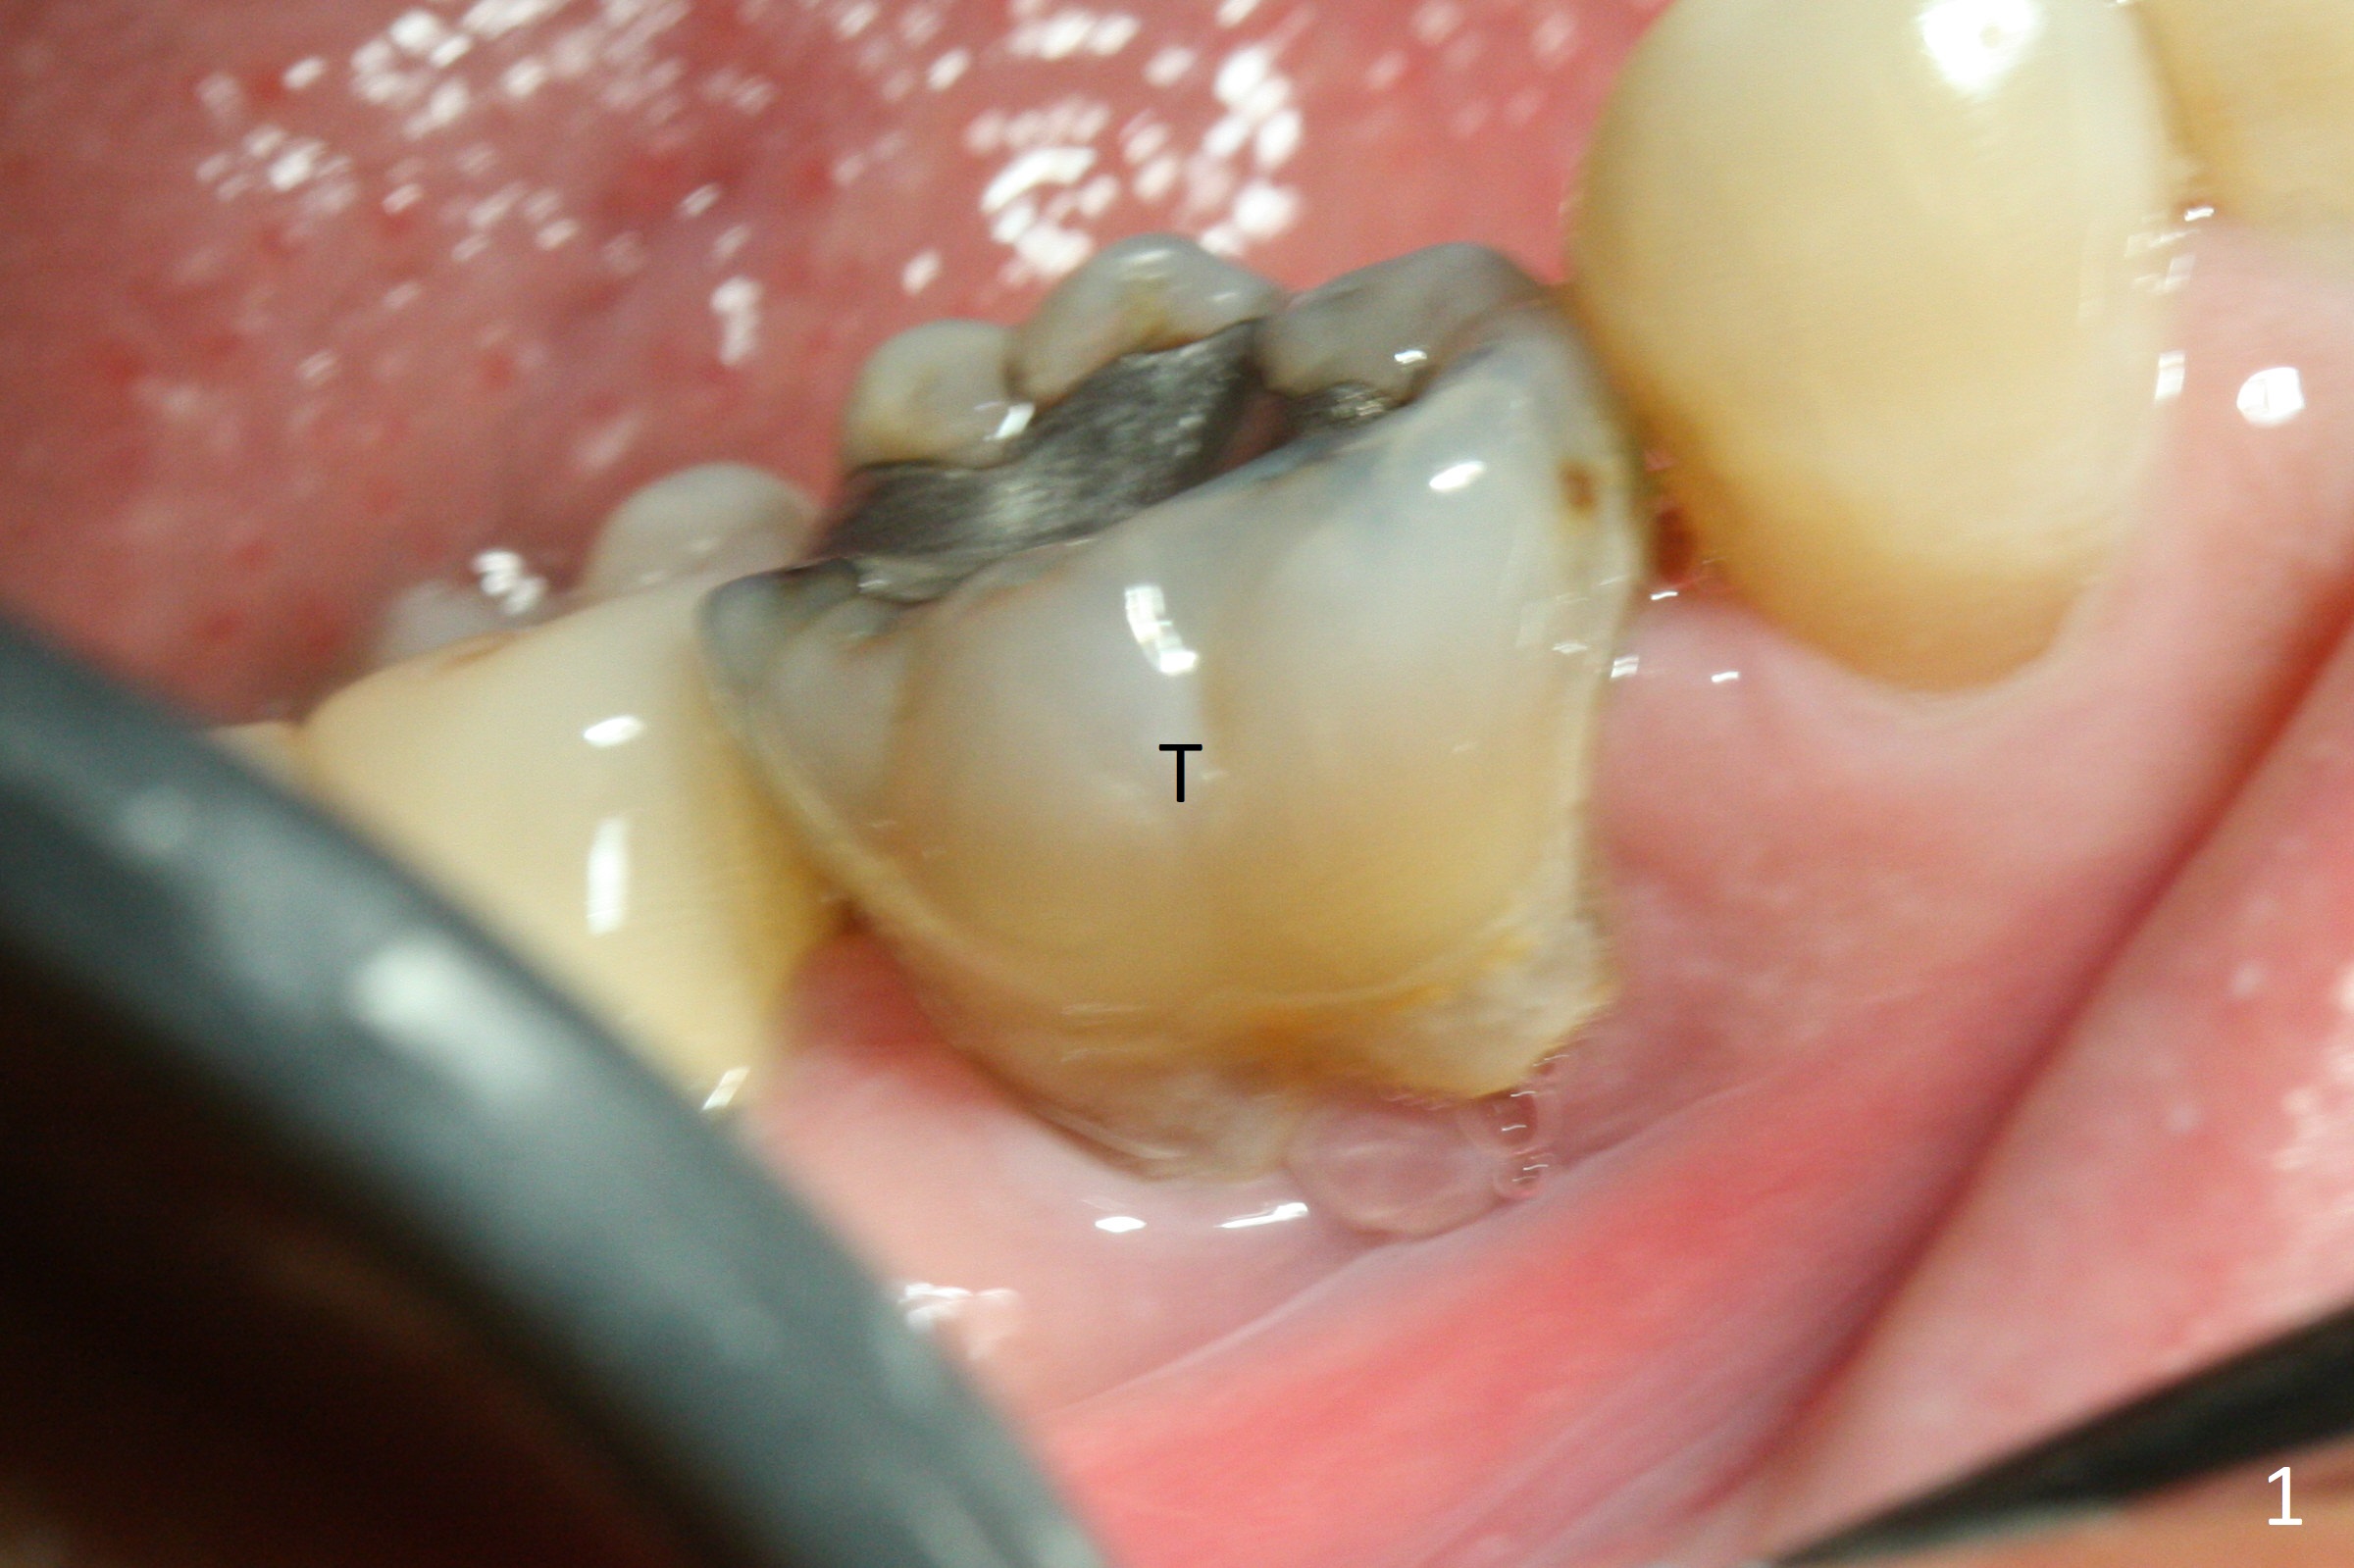

The retained deciduous tooth (lower right 2nd molar, Fig.1 T) has buccal apical infection and recession. In spite of the infection, the large-rooted deciduous tooth keeps the strong buccal plate. In contrast, an implant to replace the tooth cannot be too large. Otherwise periimplantitis will occur. The buccal extended provisional may be unable to prevent the postop bone resorption.